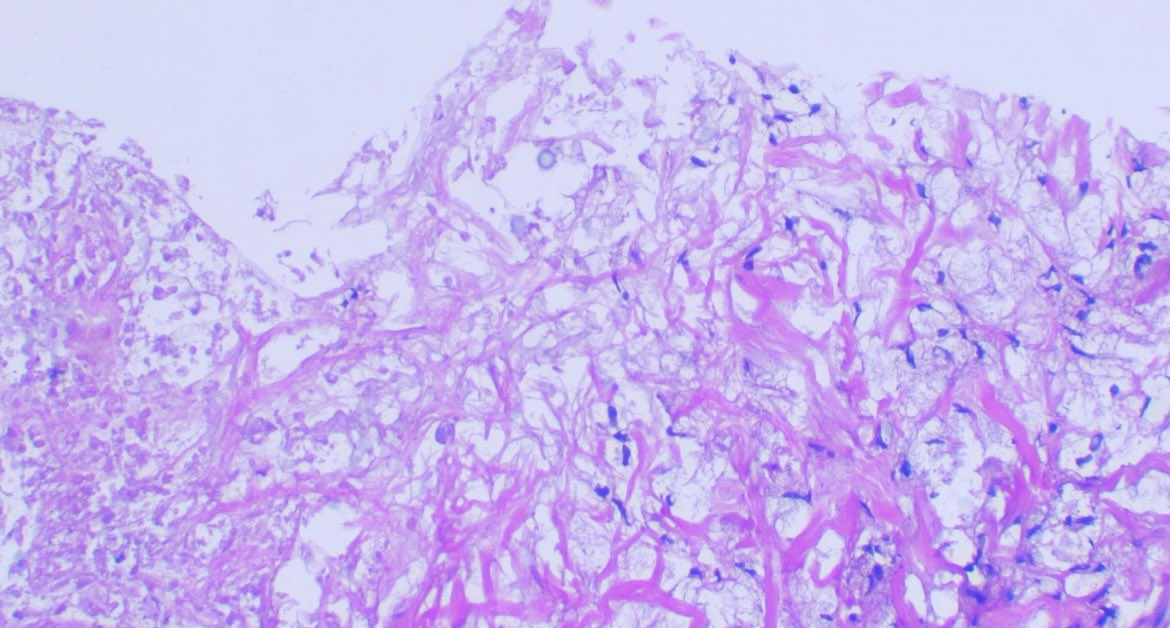

Male 75y/o Breast lesion Myofibroblastoma HE, CD34, Desmin,ER #breast #BreastCancerAwareness #path #pathology #Medicine